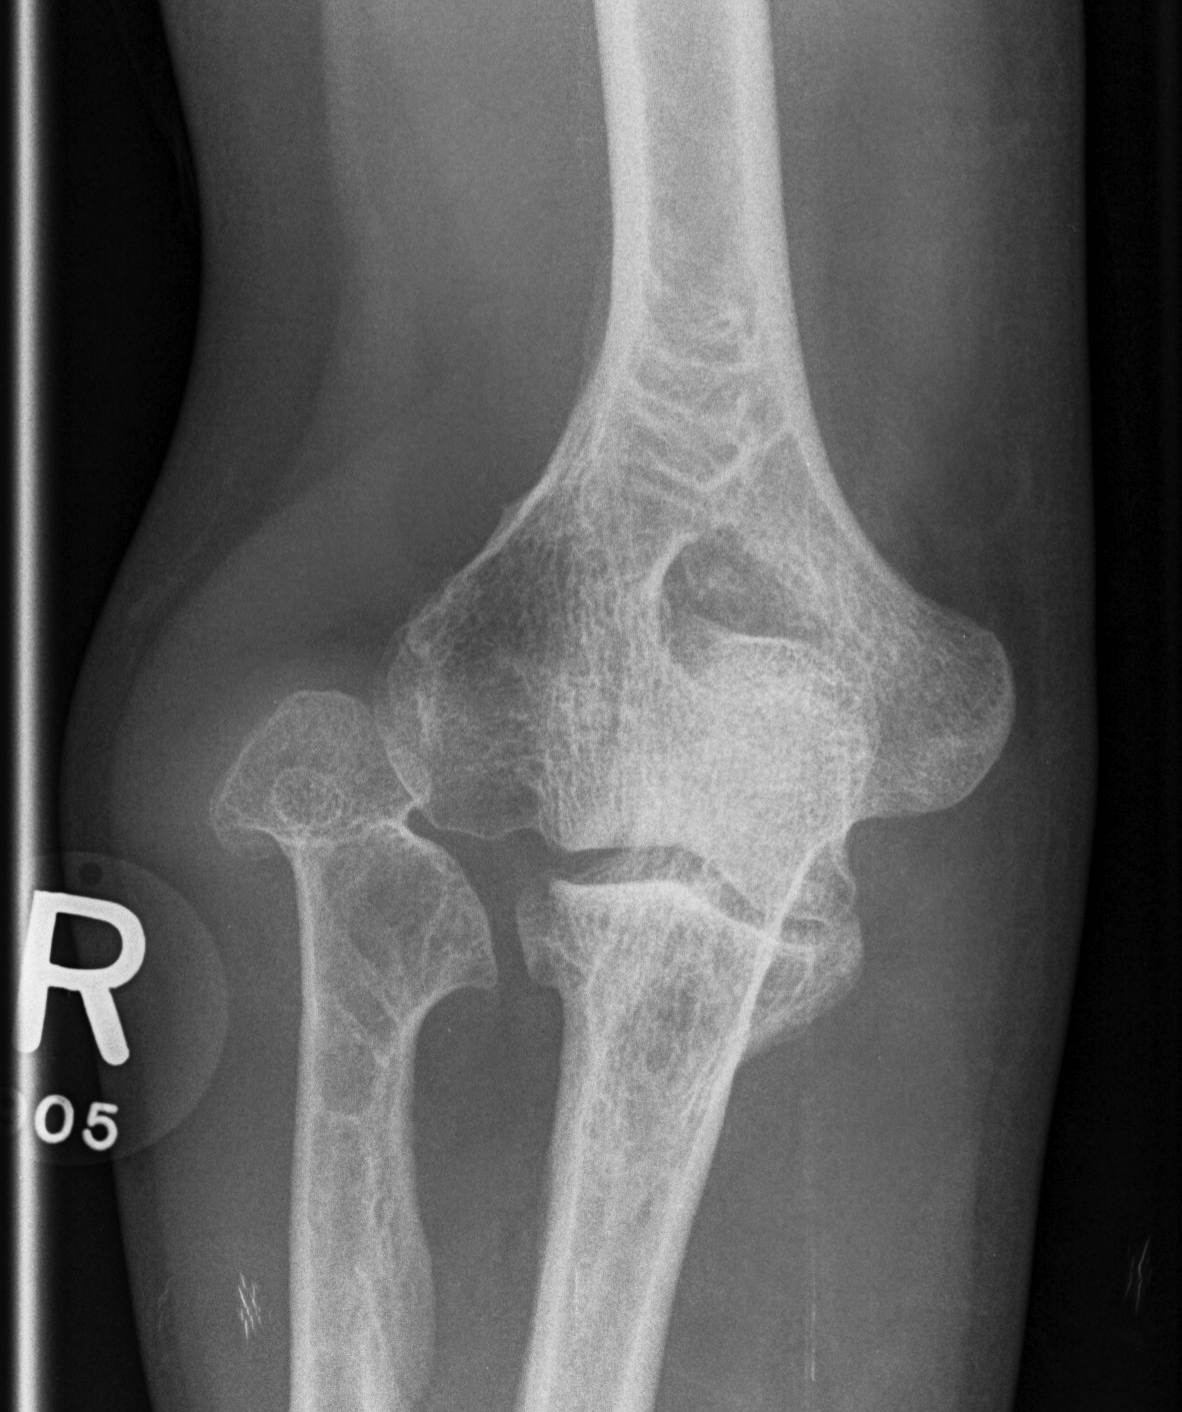

Forearm

- ulnar shortening / radial bowing / ulnar deviation of wrist

- can get radial head dislocation / carpal slip

Osteochondroma ElbowOsteochondromas Forearm 1Osteochondromas Forearm 2

Osteochondromas Forearm 1Osteochondromas Forearm 2